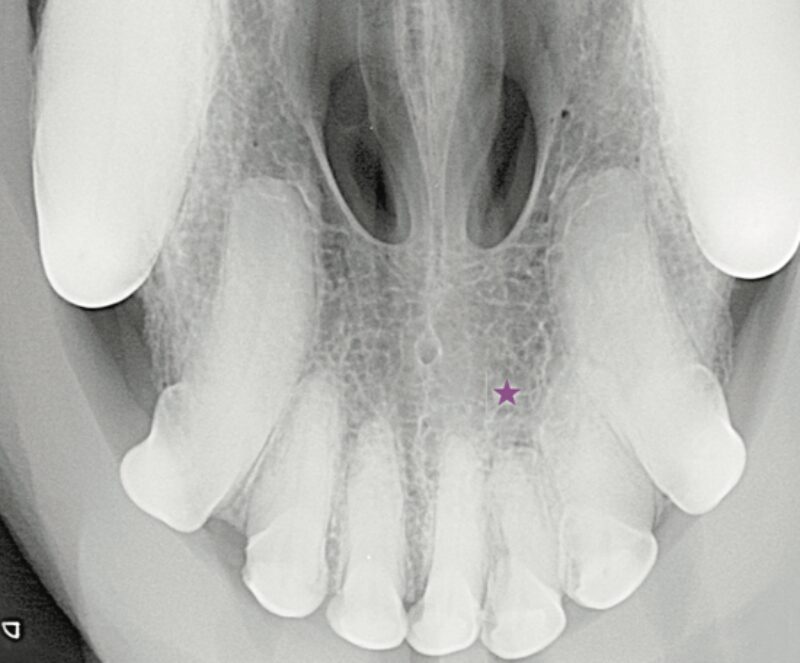

Der Röntgenbefund zeigt den doppelt angelegten I2 im Oberkiefer links sowie eine periapikale Radioluzenz (★) und einen erweiterten Parodontalspalt (▶️). Aufgrund der Überlagerung der Wurzelbereiche wie hier im linken Incisivibereich konnte dieser erst durch die Anfertigung einer intraoralen Schrägaufnahme besser beurteilt werden.

Differentialdiagnostisch sollten persistierende Incisivi – Milchzähne (▶️) ausgeschlossen werden. Sofern stomatologisch wie röntgenologisch keine Hinweise auf eine Zahnerkrankung vorliegen, kann der zusätzliche Zahn belassen werden. Allerdings wird ein Zuchtausschluss empfohlen.